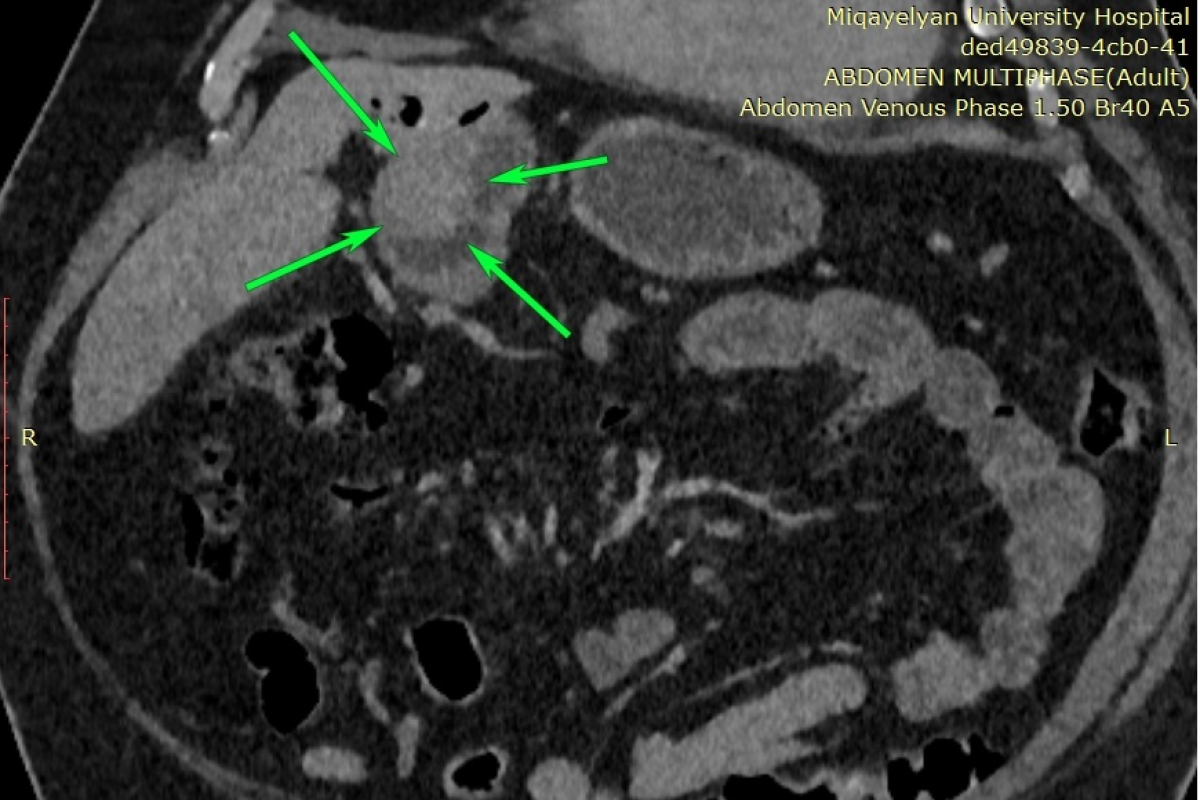

Էզոֆագոգաստրոդուոդենոսկոպիայի ժամանակ հայտնաբերվել է ստամոքսի առաջային պատի ուռուցք, որը տեղակայված էր ստամոքսաելքի շրջանում (ծառայության ղեկավար՝ Կարեն Մանուկյան): Կատարվել է նաև համակարգչային շերտագրություն կոնտրաստավորմամբ (ծառայության ղեկավար՝ Լևոն Դավթյան), որը հայտնաբերել է նշված հատվածում հստակ եզրերով ներպատային ուռուցք: